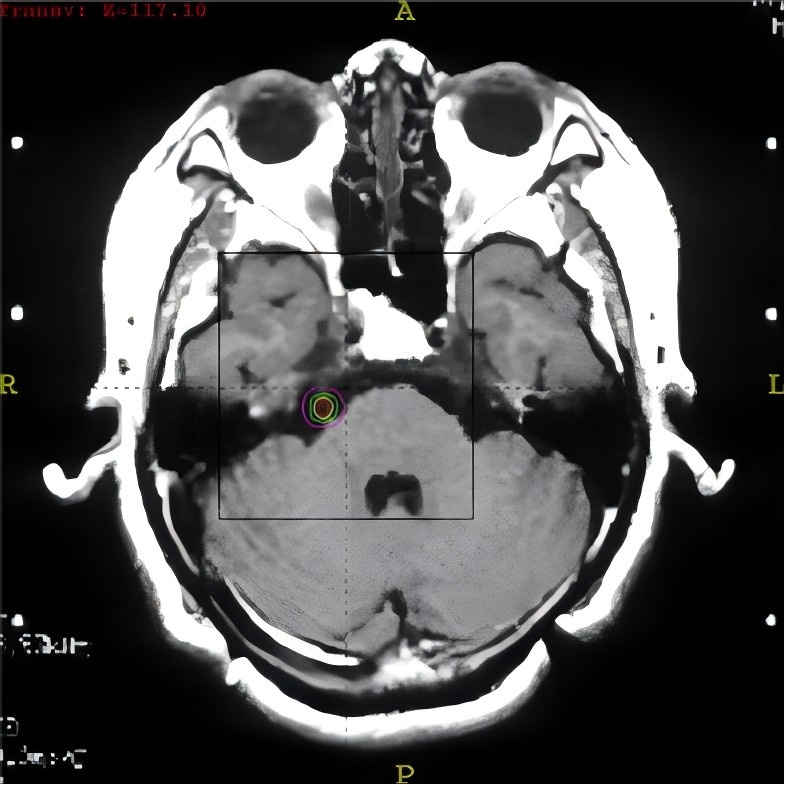

(4) 伽玛刀照射:将伽玛射线精确聚焦在三叉神经根部,通过特定照射剂量阻断痛觉传导,同时保留患者的触觉和运动功能。三叉神经由不同神经纤维组成,其中负责传递痛觉的 Aδ纤维直径最细、髓鞘最薄,对射线最敏感,易被射线摧毁,因此精准剂量的伽玛射线照射可实现阻断痛觉传导,而对触觉、运动功能的影响较小。

伽玛刀治疗的具体步骤如下:

(1) 为患者佩戴固定立体定位框架;

(2) 进行磁共振定位扫描;

(3) 医生根据扫描结果制订个性化治疗计划;

(4) 患者上机接受治疗,治疗全程实时监控;

(5) 治疗结束后,卸掉立体定位框架,对微创针眼进行包扎处理。